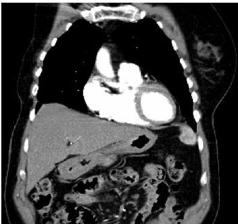

Pacientka po ablaci pravého prsu

byla přijata k plánované operaci pro nález tumoru žaludku.

Dle EUS předoperačně nález infiltrace těla žaludku bez prorůstání

skrz m. propria, z biopsie nález karcinomu žaludku, difúzního

typu.

Předoperační staging T1N0M0